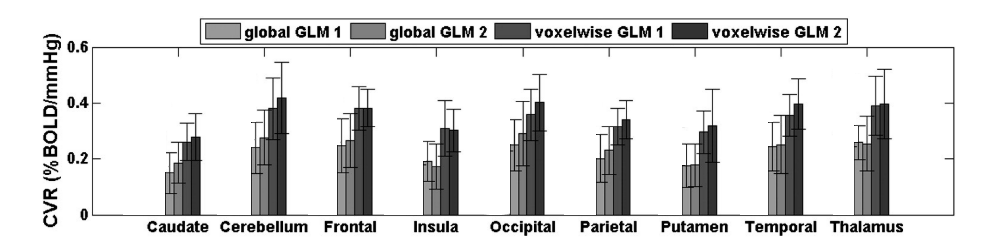

Methods: CVR and lag maps

CVR and lag maps: L-GLM with each lagged regressor and nuisance regressors (12 motion parameters and low frequency trends), voxelwise selection of the lagged model with highest explained variance (R²), normalisation to MNI152 template (2.5 mm isotropic)

We compared four pipelines:

- L-GLM with motion parameters (see above, SimMot): $$ Y = P_{ET}CO_2{hrf}_{vx} + Mot + Poly + n $$

- Non-optimised CVR map (measurement delay only, Non Opt): $$ Y = P_{ET}CO_2{hrf}_{bulk} +n $$

- L-GLM without motion parameters (NoMot): $$ Y = P_{ET}CO_2{hrf}_{vx} + n $$

- L-GLM without motion parameters, motion regressed out before (SeqMot): $$ [Y \perp (Mot,Poly)] = P_{ET}CO_2{hrf}_{vx} + n $$

We compared four pipelines:

- L-GLM with motion parameters (see above, SimMot): $$ Y = P_{ET}CO_2{hrf}_{vx} + Mot + Poly + n $$

- Non-optimised CVR map (measurement delay only, Non Opt): $$ Y = P_{ET}CO_2{hrf}_{bulk} +n $$

- L-GLM without motion parameters (NoMot): $$ Y = P_{ET}CO_2{hrf}_{vx} + n $$

- L-GLM without motion parameters, motion regressed out before (SeqMot): $$ [Y \perp (Mot,Poly)] = P_{ET}CO_2{hrf}_{vx} + n $$

Results: model comparison

Moia et al. 2021 (NeuroImage)

CVR amplitude

CVR lag

CVR amplitude

CVR lag